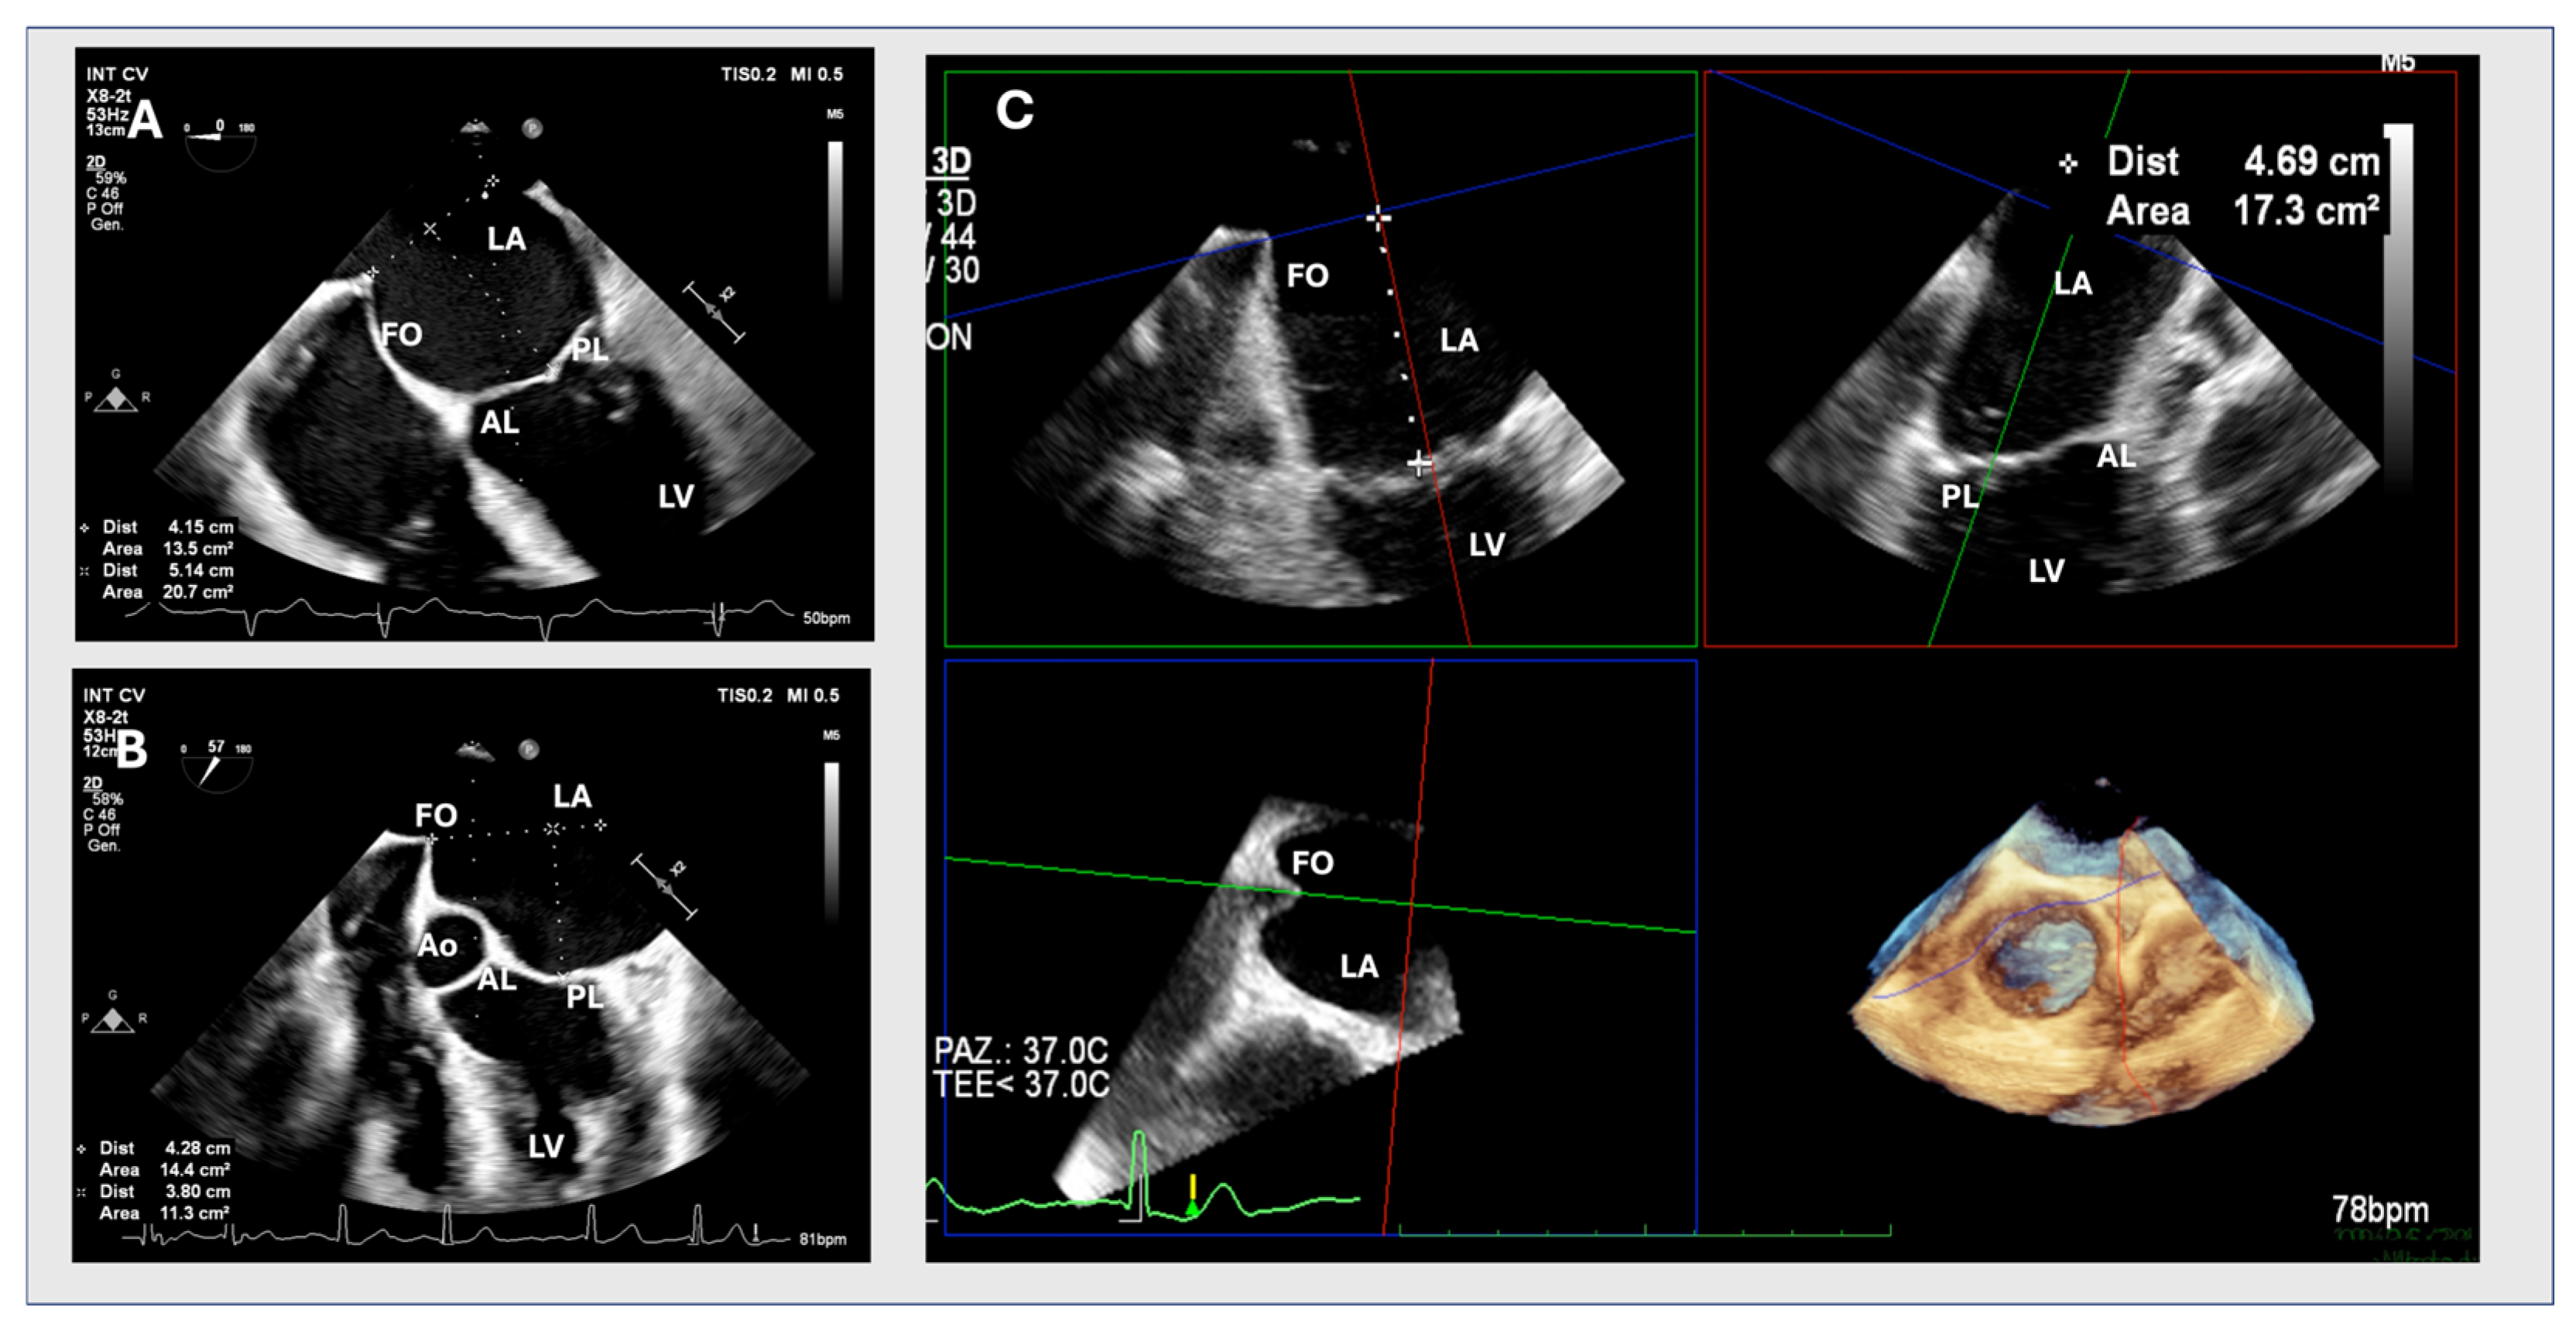

2.1. Two-Dimensional Method

2.2. MPR Method